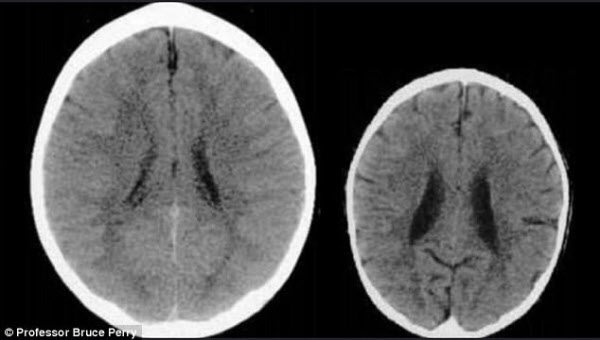

아래 사진 속 두 개의 뇌 CT 촬영 사진은 모두 세 살배기 아이의 뇌다.

하지만 같은 나이에 성장 속도가 비슷한 아이의 뇌라고 보기엔, 크기 차이가 현저하다.

또 오른쪽 뇌는 내부 발육도 훨씬 더디다.

양육 방식에 따라, 세살짜리 아기의 뇌는 크기와 모양에서 큰 차이를 보였다/ 브루스 페리 교수

미국 텍사스아동병원의 정신치료학과 교수인 브루스 페리 교수는 아기가 받은 ‘사랑’(왼쪽)과 ‘학대(오른쪽)’가 이런 차이를 만들었다고 밝혔다.

왼쪽 뇌의 아기는 유복한 환경에서 사랑을 받고 자라 ‘정상적인’ 뇌의 모습을 보여주지만, 왼쪽 아기는 루마니아의 한 고아원에서 입양됐으며 무시와 학대 속에서 심한 감정적 트라우마를 겪으며 자랐다.

페리 교수는 “두 사진은 성장하는 뇌에 학대가 끼치는 부정적 영향을 단적으로 보여준다”고 밝혔다. 오른쪽의 세 살짜리 아이의 뇌는 뇌실이 크고, 피질이 위축된 상태다.

그는 "오른쪽 아기의 뇌 사진을 보면, 자라면서 따듯한 손길이나 청각, 냄새, 시각 등의 자극을 받지 못해 현재 심각한 ‘감각 박탈’을 겪으며 극도의 학대를 받아왔다고 추정할 수 있다”고 말했다.

아기는 집중력이 떨어지고 환각 등을 겪을 수 있다.

성장기 아기에게 제대로 사랑을 쏟지 못하면, 나중에도 아기의 뇌 발달 속도는 '정상적인' 아기 뇌를 좇아가지 못한다/

오른쪽 아기와 같은 뇌의 구조적인 손상은 ‘발달 지연’과 ‘기억력 감퇴’로 이어진다. 피질 위축 증상은 보통 치매에 걸린 노인에게서 발견되는 증상이다. 특히 아이가 신체적 학대를 당하면, 즉시 아이의 뇌에 심각한 손상이 가해진다고 한다.

비슷한 현상으로 부모가 아기가 말을 안 듣는다고 몸을 마구 흔드는 ‘흔들린 아기 증후군’을 겪은 아기도 뇌세포와 혈관이 파괴돼, 마비·성장 장애·사망을 초래할 수 있고, 장기적으로도 아이의 감정 발전에 치명적인 악영향을 미쳐 커서도 인간 관계를 맺기가 힘들어진다.

작년 미국 과학자들의 연구에서도, 학대 받은 아기의 뇌가 자라는 속도는 ‘정상적인 아기’ 뇌에 비해 절반에 불과했다. 특히 6세 이하까지의 양육 방식이 아이의 뇌 발달에 큰 영향을 미쳤다. 127명의 아이들의 뇌를 추적 관찰한 이 연구는 “나중에 부모가 좀 더 사랑으로 아이를 대해도, 이미 발육이 늦어진 뇌는 ‘정상적인 환경’에서 자란 아이의 뇌를 좇아가지 못한다”고 밝혔다.